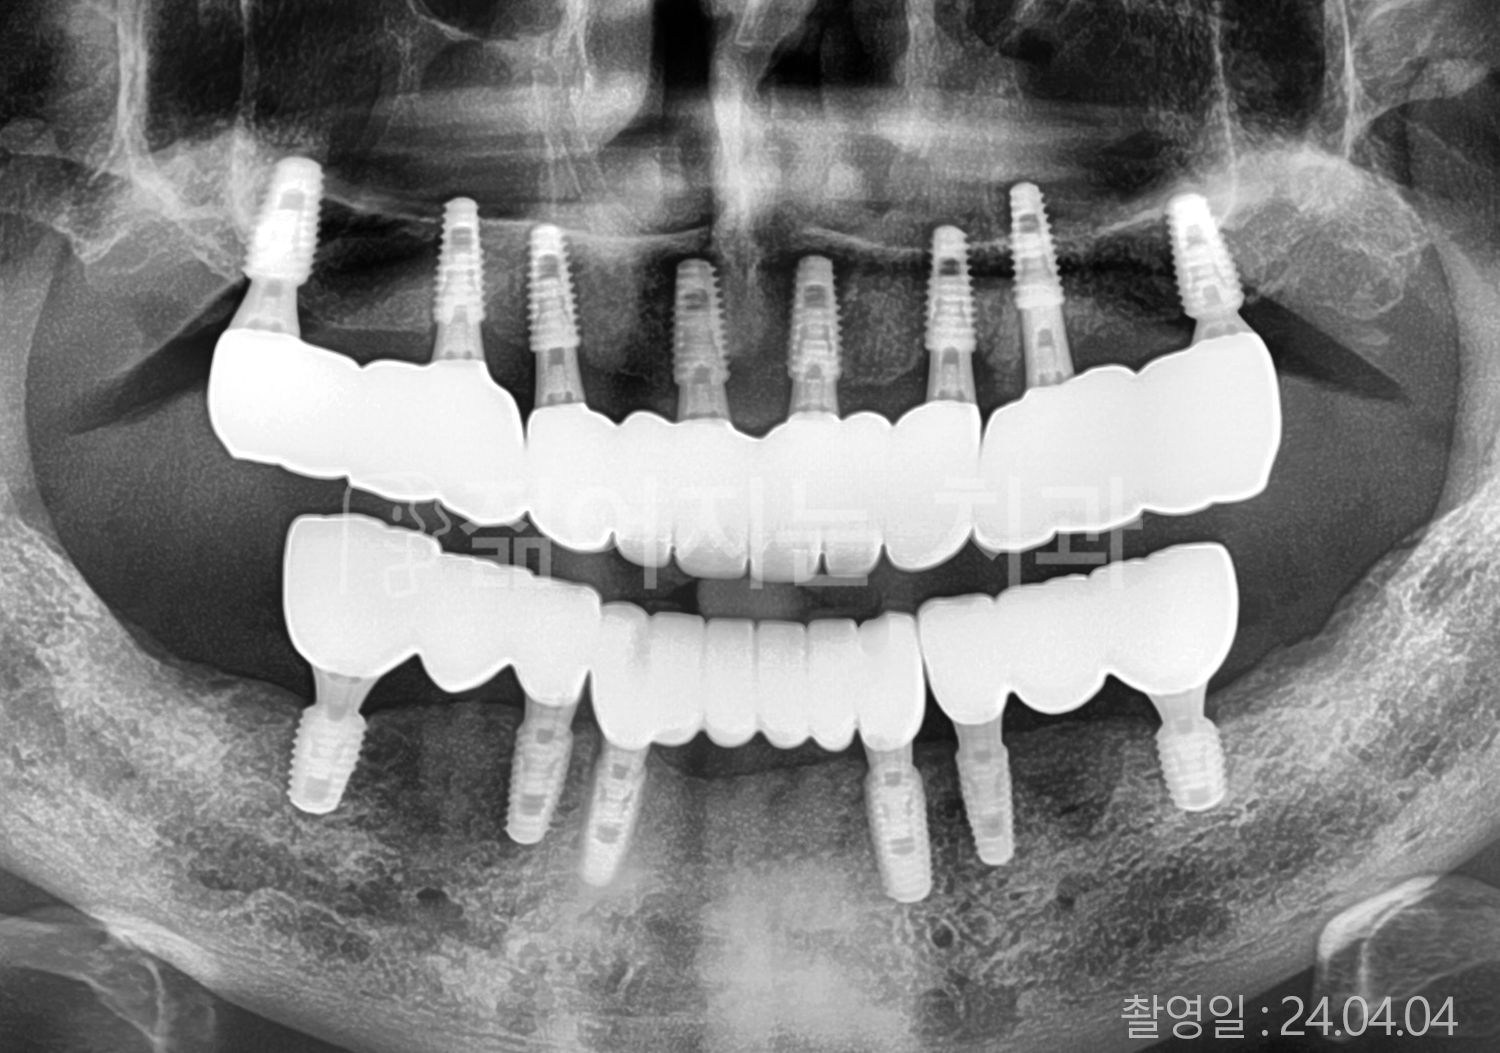

• 60대 전체치아 10개 이상 임플란트